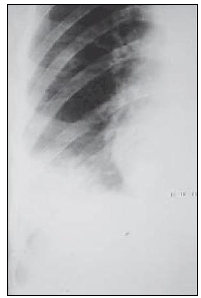

“Paciente apresenta o seguinte exame de radiografia torácica.”

Assinale a alternativa que apresenta corretamente o sinal presente no exame.

Sinal de Luftsichel.

Sinal de Westermark.

Sinal da sobreposição hilar.

Sinal da corcova de Hampton.